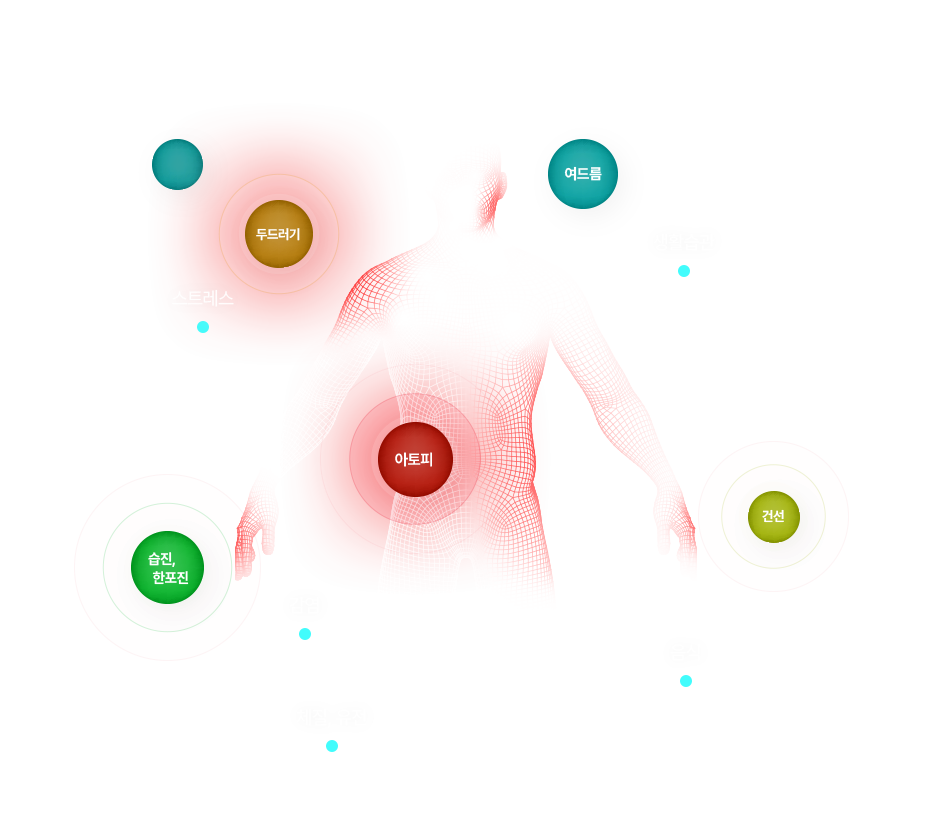

아토피의 치료 원리

아토피는 인체 전반적인 면역의 문제로 발생하는 종합면역질환으로

인체 면역 밸런스의 정상화가 치료의 핵심입니다.

위장, 소장, 대장 등 소화기관과

연관된 증상을 동반

아토피 환자

공통 특징

수면장애, 우울증, 화병, 스트레스 등

뇌신경 계통 증상을 동반

‘장+뇌+피부’는 유기적으로 작용